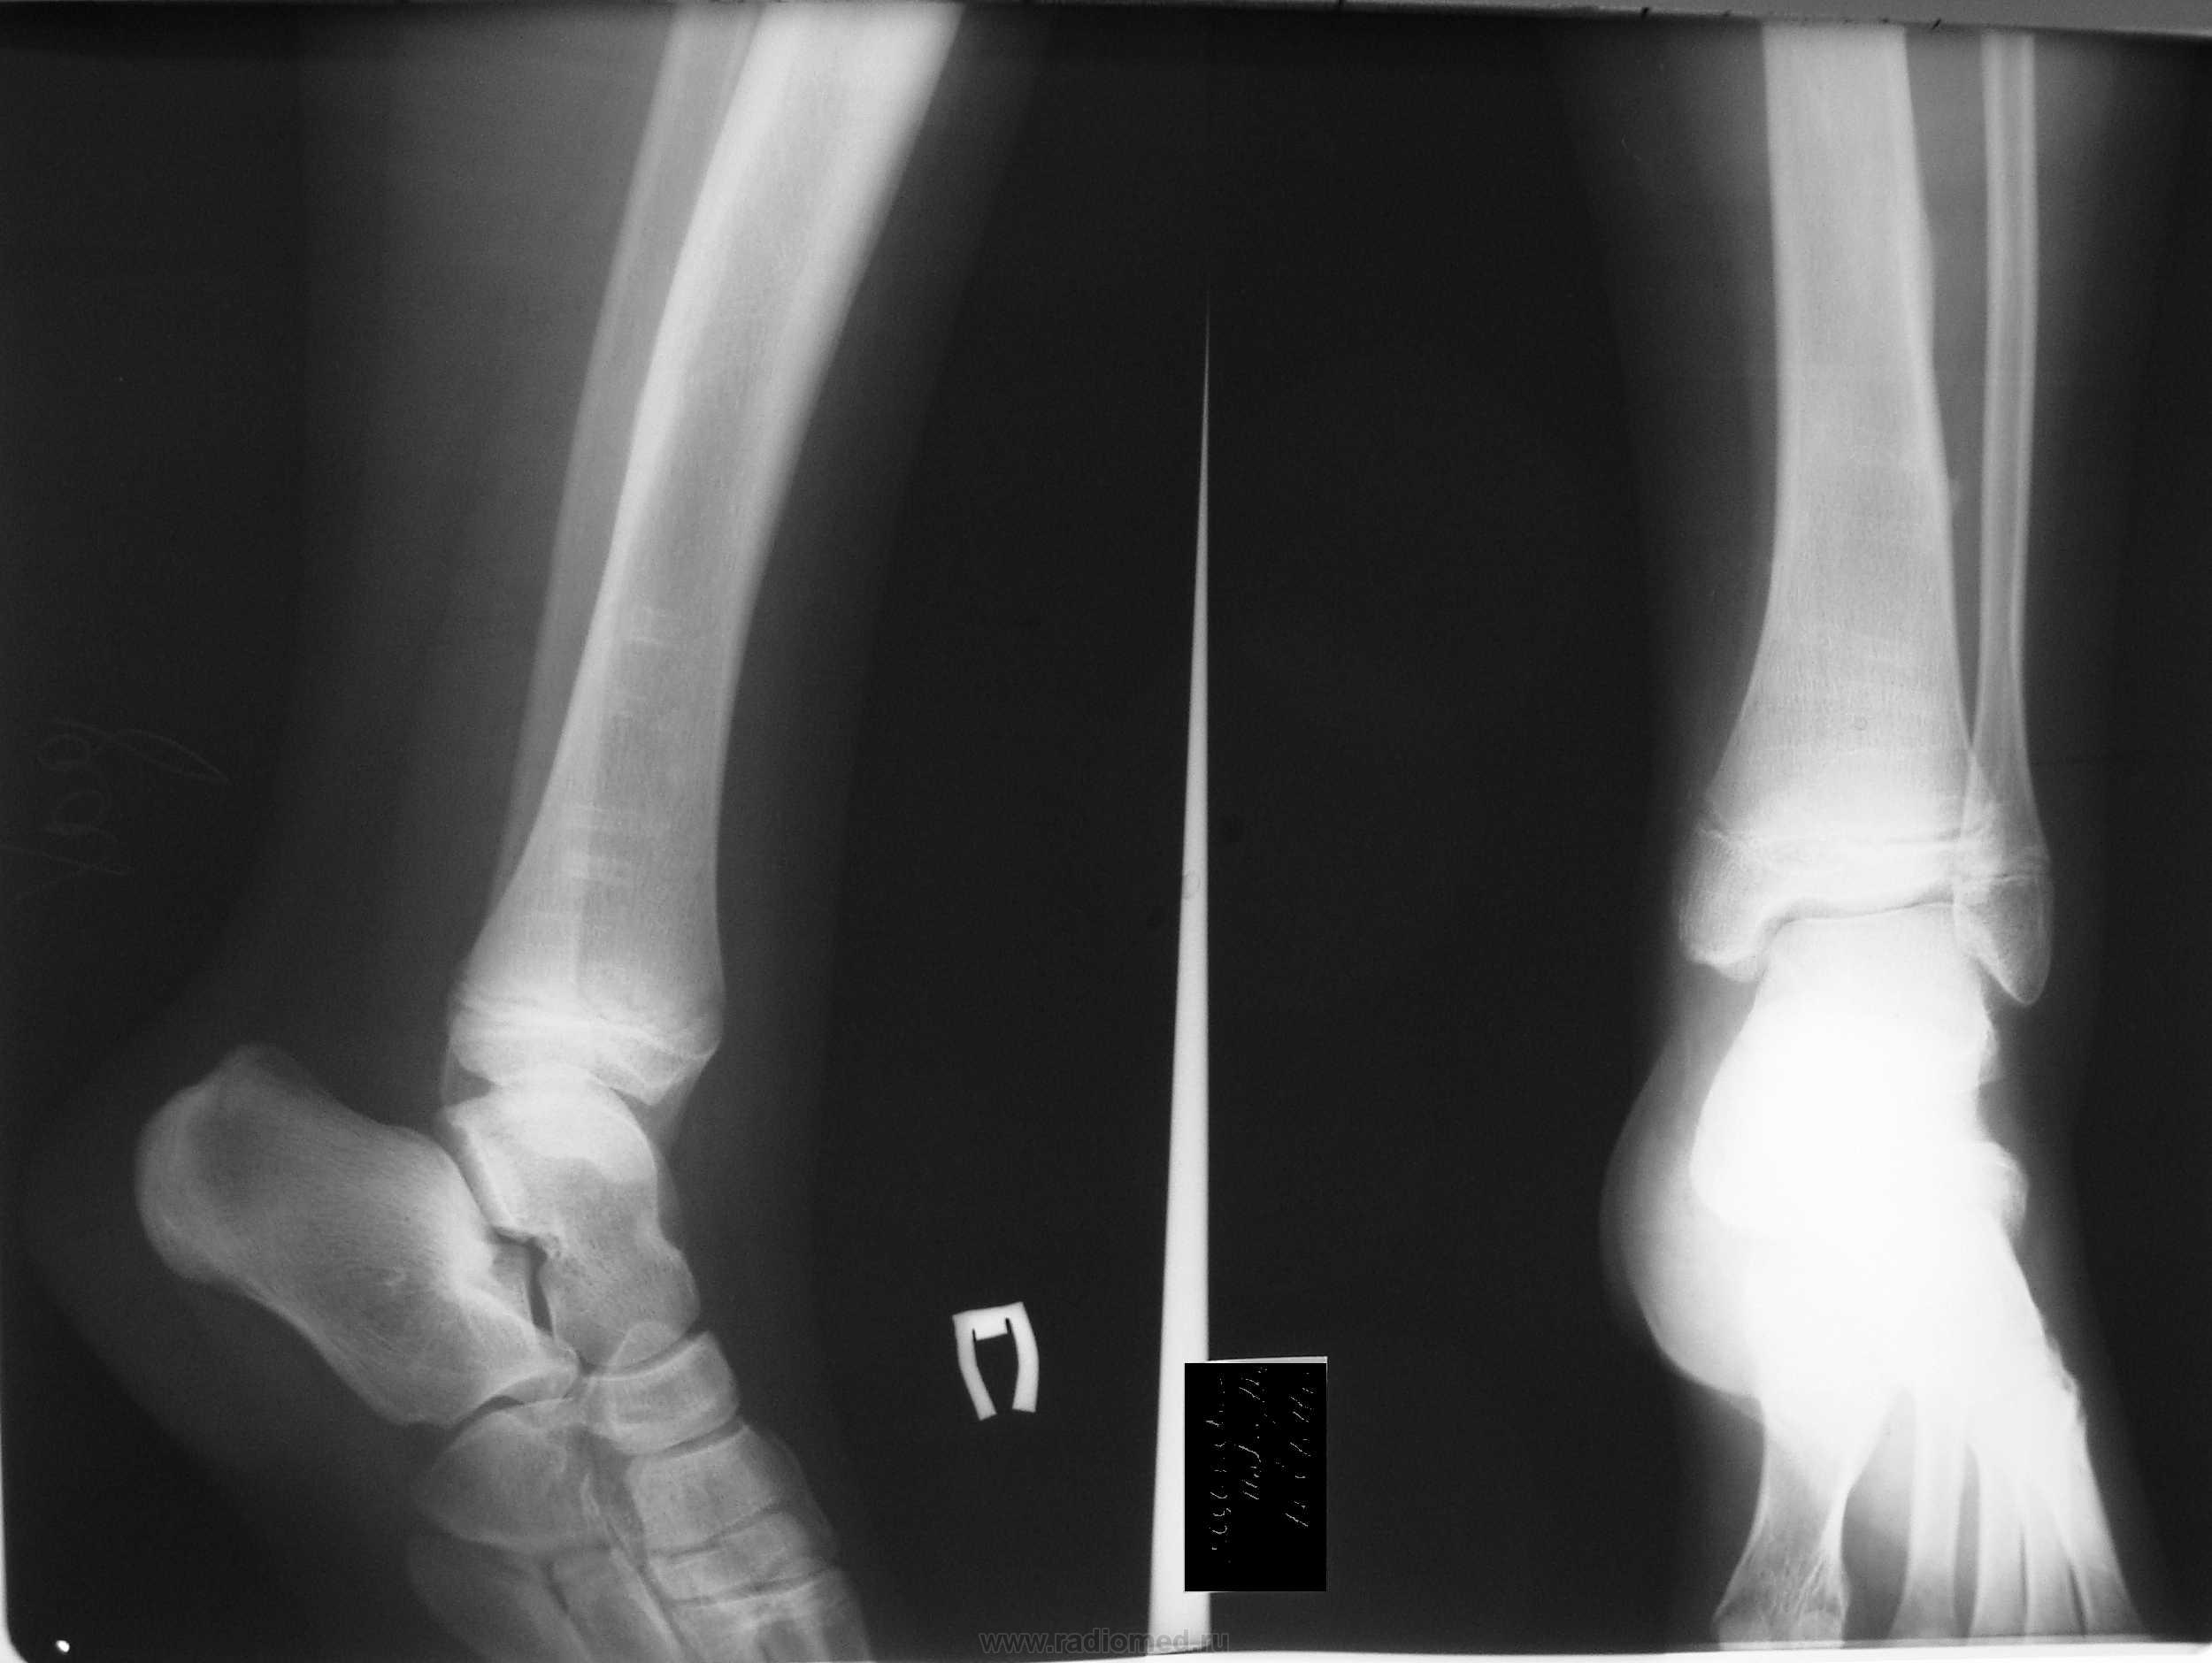

Девочка, 12 лет предъявляет жалобы на боли в правом голеностопном суставе при нагрузке. Два года назад был перелом нижней трети большеберцовой кости с фиксацией винтами. Ваше мнение?

А вам что не нравится? Вроде ничего плохого не видно, только эквинус стопы не нравится, или это такая укладка?

это такая укладка. не нравится внутрений контур большеберцовой кости, или это такие последствия от винтов?

Наверное, наружный контур? Я думаю, это от винтов.

Кажется остеоид-остеома в пяточной кости

В глубине кости просветление между шейкой и телом. Картинку с указателем транслировать не удалось

в костях патологии не вижу (помимо того чего было) может стопу с нагрузкой на плоскостопие сделать если есть предпосылки (я имею в виду после консультации с ортопедом или травматологом).